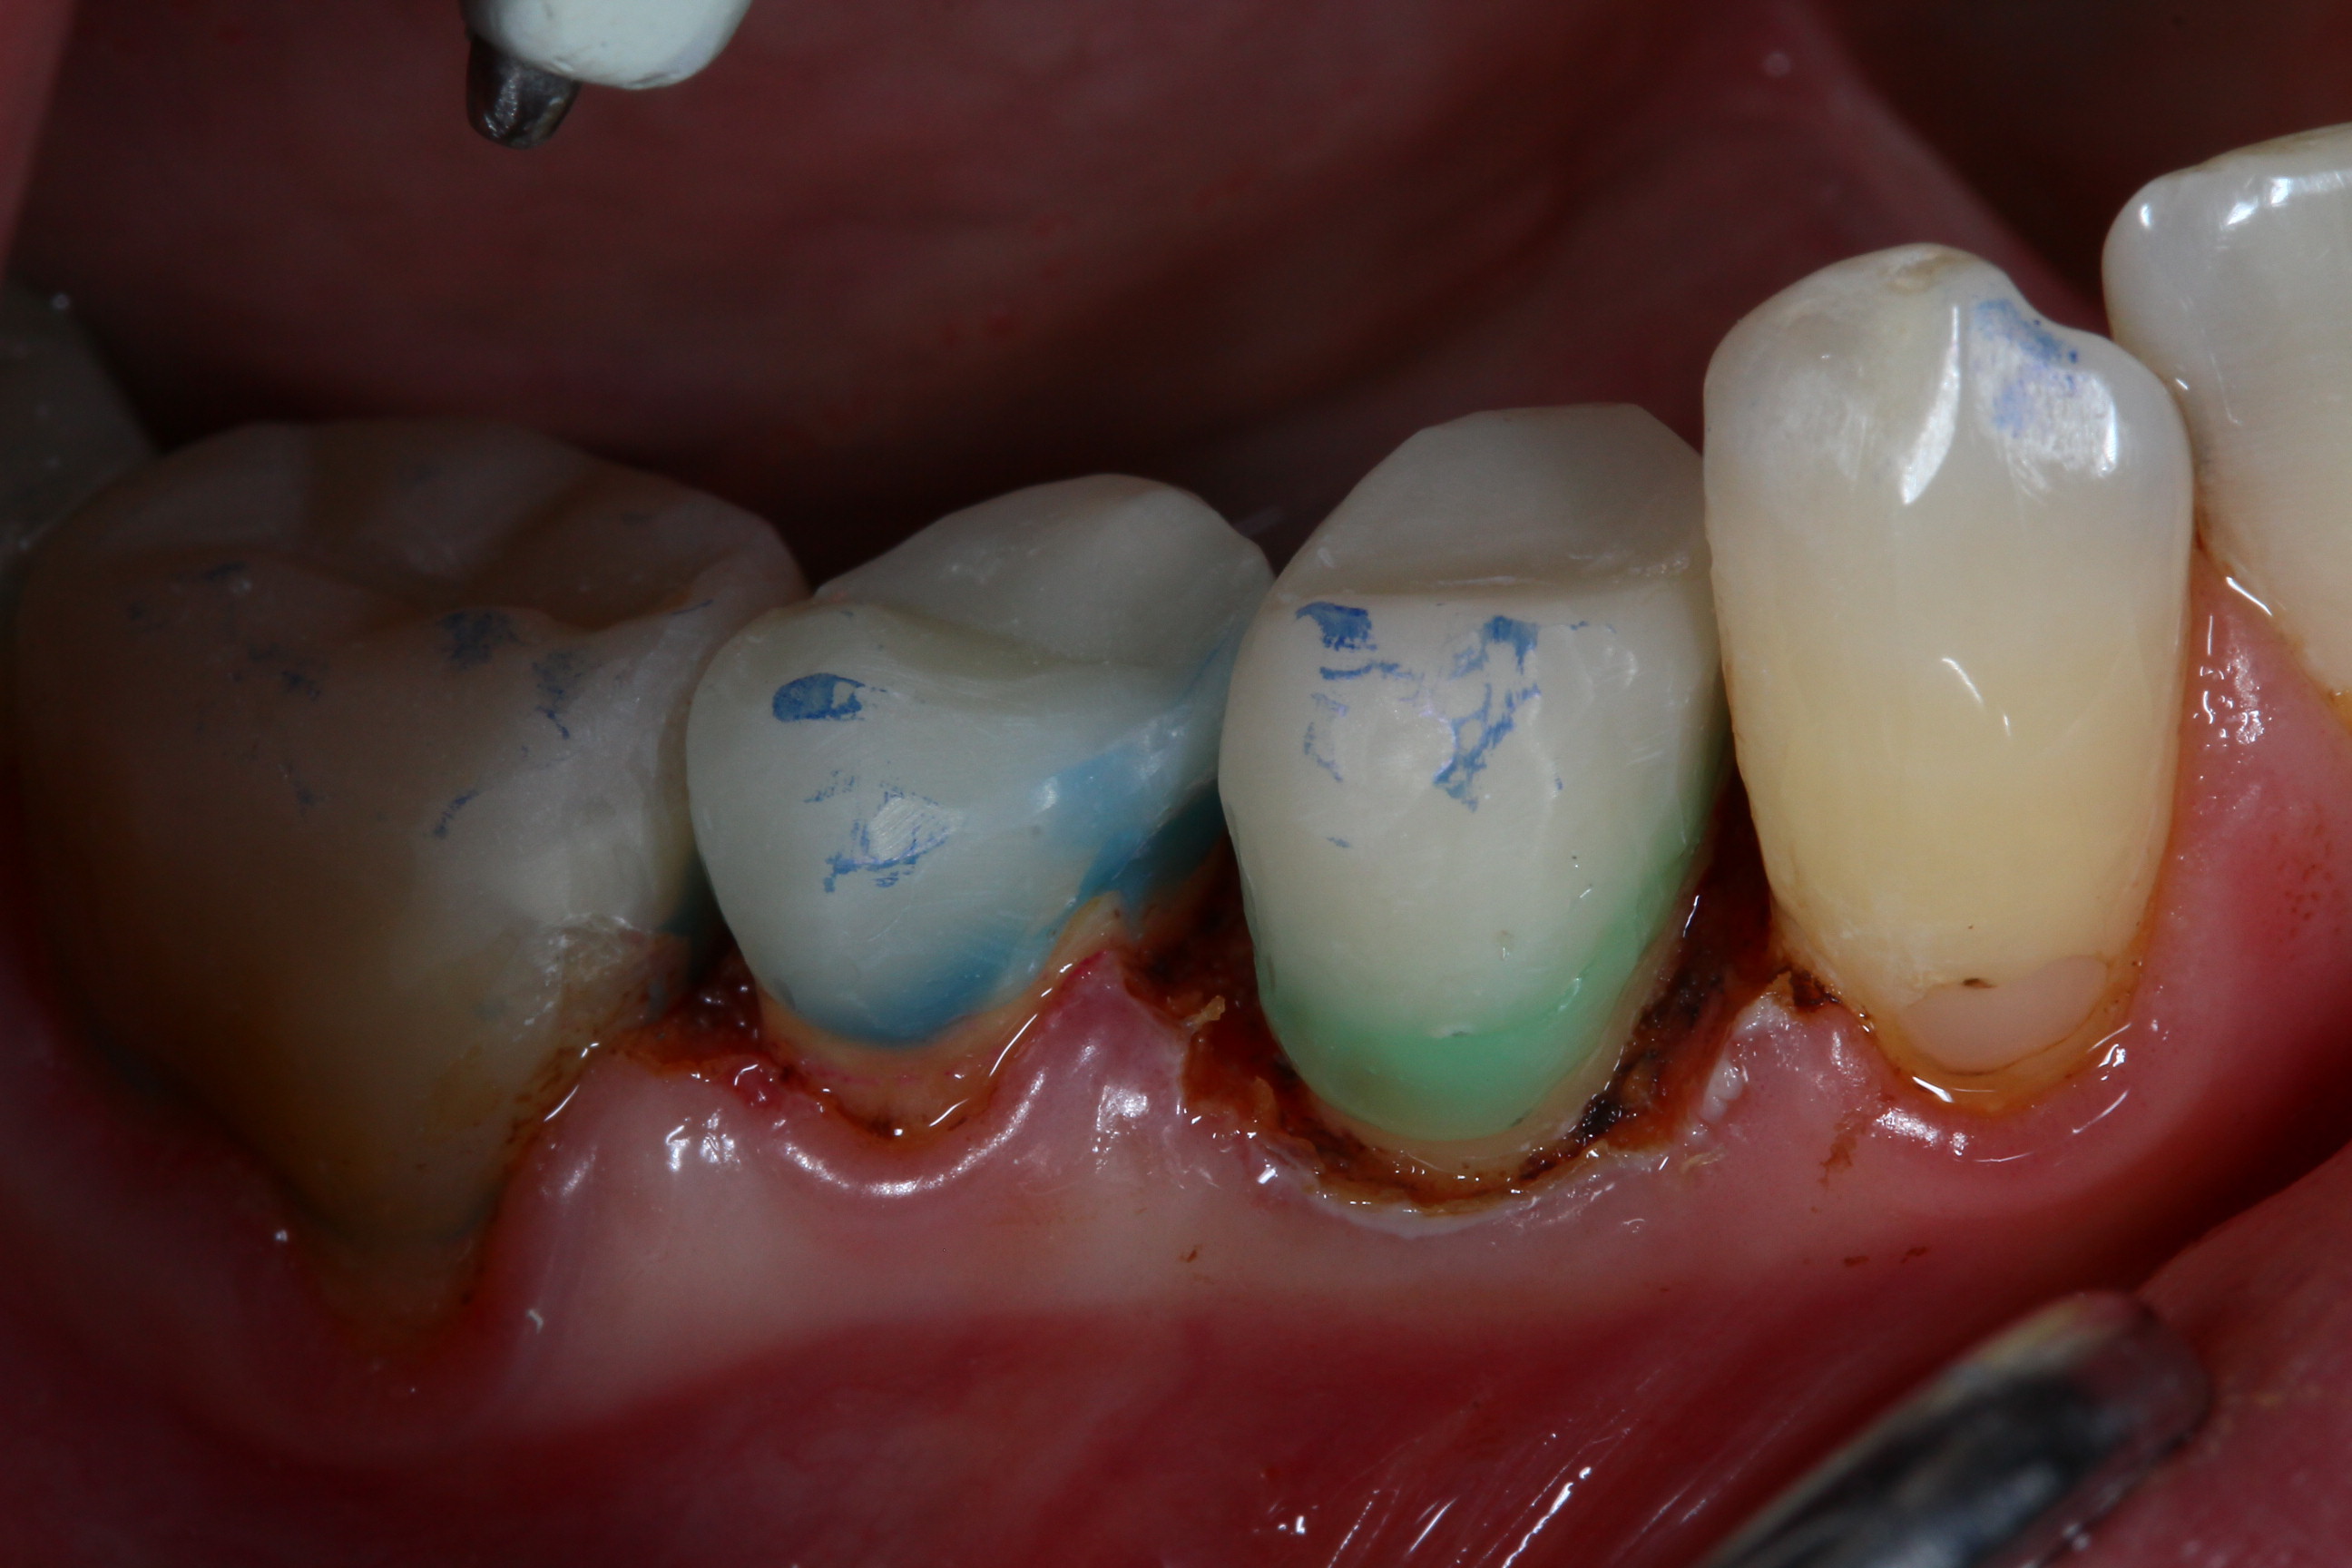

A5 Fertige Core AUfbauten Veröffentlicht 10. November 2012 am 2592 × 1728 in Vor der Endo ist nach der Endo: Aufbaumaterialien